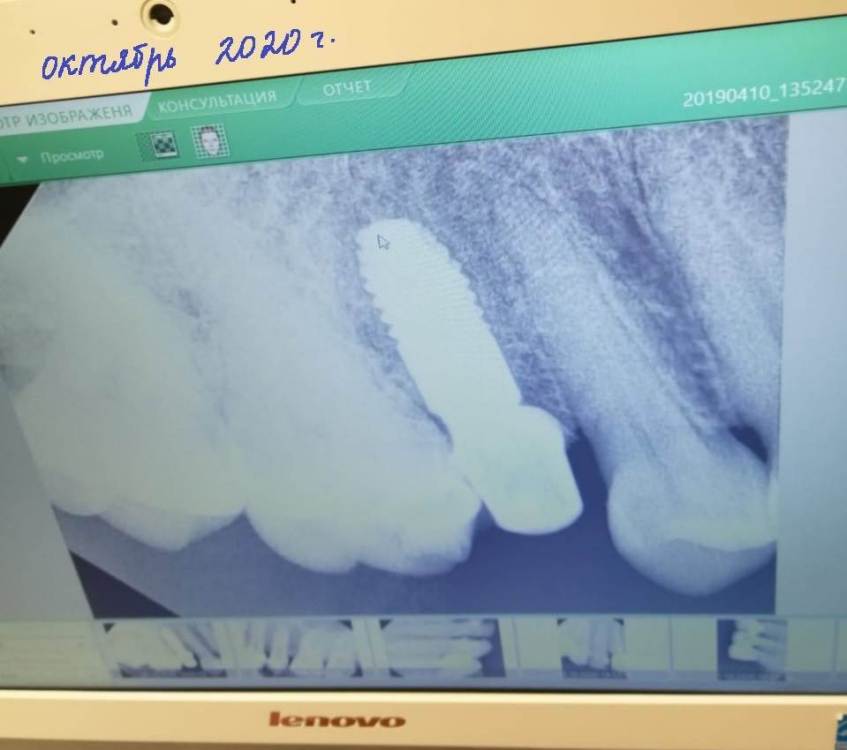

Dashik Опубликовано 26 октября, 2023 Поделиться Опубликовано 26 октября, 2023 Добрый день, уважаемые врачи! Мне 41 год, 4,5 года назад я установила имплантат на месте 5 зуба, через 5 месяцев на него была установлена временная коронка, десна время от времени кровила, просто не обращала на это уже внимание. В конце октября 2020 года доктор снял коронку, подшлифовал, сделал снимок, сказал, что эта коронка останется постоянной и прослужит от 5 и выше лет, объяснив тем, что цирконием или металлокерамикой я снесу себе имплантат, челюсть под нагрузкой. На ночь одевала силиконовую каппу от бруксизма. За пять лет она особо не протерлась, есть некоторые дырочки на 6 зубах. Перед постановкой имплантата я посетила МГМСУ им. Евдокимова, там на консультации сказали, что прикус нормальный в детстве сделали, не было противопоказаний к имплантации. В 15 лет я носила пластину на верхней челюсти полгода. Ретенированные 8-ки были удалены в 22 года по рекомендации лечащего врача. Буквально неделю назад над коронкой появился небольшой карман, кровит, справа от которого заметна небольшая округлая выпуклость белого цвета. По утрам карман беловатый. Десна вокруг коронки воспалена, болит и кровит, но не так как раньше чуть-чуть, в зеркале весь ободок между десной и имплантатом в крови после еды или чистки зубов. Ирригатором пользуюсь постоянно, зубной нитью тоже, только она не помогает. Контактный пункт между 4 зубом и коронкой отсутствует уже года 3, нить проходит свободно, ничего не прочищая, а между коронкой и 6 зубом, наоборот, с трудом, иногда кажется, что коронка отклеится. Я своему врачу говорила о том, что нить стала проходить без щелчка, но он сказал, что всё нормально. В межзубные промежутки забивается пища, тем самым вызывая раздражение сосочков. От этого они приподнялись к десне, воспалены, видны черные треугольники. Полоскаю неделю травами шалфея и ромашки, наношу Метрогил, но не помогает. Вчера сделала снимок в клинике рядом с домом. Очень волнуют следующие вопросы 1. Что делать дальше? В чём причина образования кармана? Всё было хорошо, десна ровно прилегала к коронке и сосочки были отличные, никаких черных треугольников, ничего не беспокоило. 2. Как изменилась костная ткань по сравнению с 2020 годом? 3. У кого-то из врачей форума были ситуации, когда пластмассовая коронка оставалась на совсем? Какой срок службы в среднем пластмассовых коронок? 4. Как отражается пластмассовая коронка на здоровье пациента? Микрочастицы оседают у меня в желудке, кишечнике. Она не может вызывать аллергию, у меня появилась сильная экзема на двух руках через полгода после установки? Фото снимков 2020 года, вчерашнего и слепки челюстей (имплантат с заглушкой уже установлены) прилагается. Пыталась сделать также фото десны, не информативно, прикреплять не стала. Огромное спасибо за потраченное время 1 Ссылка на комментарий